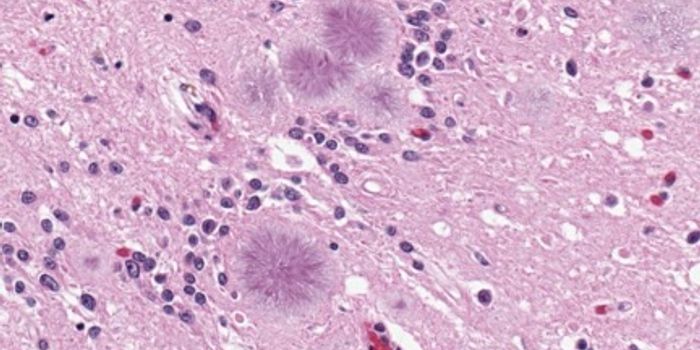

APR 14, 2016Clinical & Molecular DXPrion diseases are rare and deadly diseases of the brain. Once infected, the prion particles self-propagates and convert ...